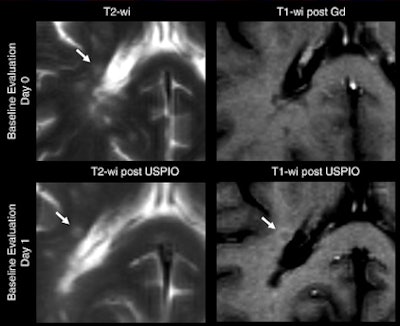

| MR images were obtained at baseline in a 49-year-old woman with progressive multiple sclerosis prior to treatment. Right periventricular lesion seen on axial T2-weighted image did not enhance on T1-weighted image obtained a few minutes after gadolinium injection, whereas images obtained 24 to 48 hours after USPIO injection show mild enhancement at T1-weighted imaging with no signal loss at T2-weighted imaging (arrows). All images courtesy of Radiology. |

All 47 lesions enhanced by USPIO (28 lesions with USPIO and gadolinium; 19 with USPIO alone) exhibited high signal intensity on T1-weighted MR images. Twenty-five (53%) of the 47 lesions had low signal intensity on T2-weighted images and even lower signal intensity on T2*-weighted images at the same location.